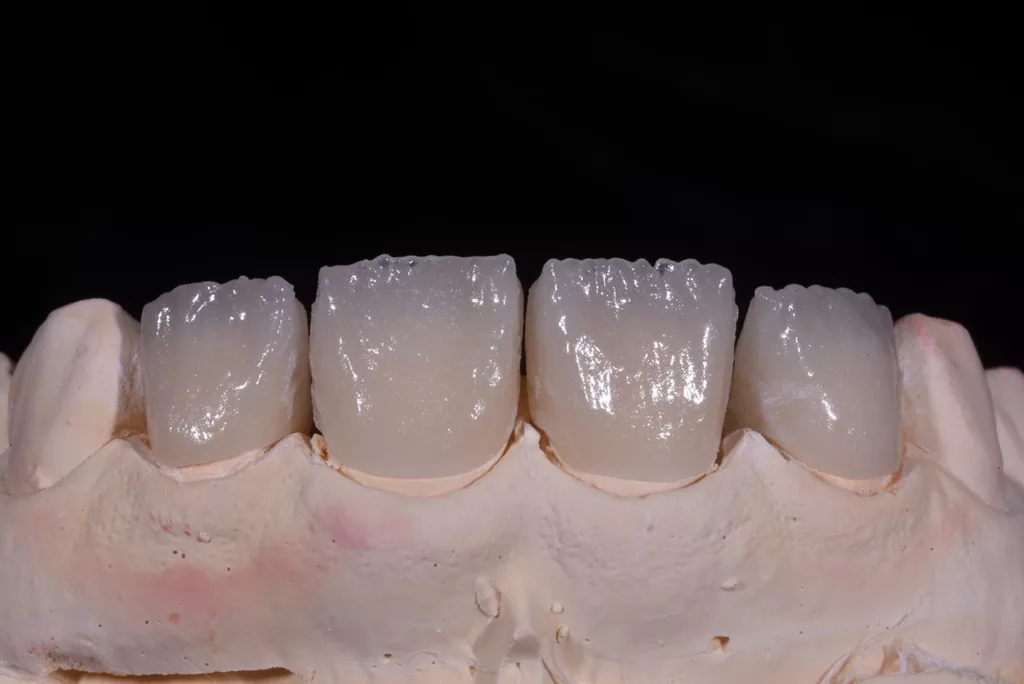

Die Kronen wurden in diesem Fall aus dem Material IPS e.max® ZirCAD Prime Esthetic von Ivoclar angefertigt. Die Transparenz des gewählten Zirkoniumdioxids ermöglichte die Fertigung dünner Kronen von 0,5 mm und gleichzeitig eine präzise Farbreproduktion ohne dicke Schichtung. Das Stumpfdesign wurde so gewählt, dass das Zirkoniumdioxid bis zur Inzisalkante reichte, um Schneidekantenfrakturen zu vermeiden. Die Schichtung erfolgte durch Auftragen von IPS e.max® Ceram Dentin-Pulver (OE1, OE2 und T1) auf das Grundgerüst (Abb. 57 bis 63).

Die fertigen Kronen nahmen die natürliche Zahnfarbe auf und überzeugten durch eine außergewöhnliche Transparenz. Obwohl die Präparationsrichtlinien für Frontzähne eine Kronendicke von 0,8 mm vorsehen, erfolgte aufgrund der Vitalität der Zähne eine möglichst geringe Präparation. Zwar erschienen die beiden mittleren Schneidezähne zunächst etwas kürzer, aber tatsächlich wurde die Länge der Kronen unter Berücksichtigung der aufgezeichneten Frontzahnführung der Patientin angemessen bestimmt. Durch diese Vorgehensweise lässt sich sicherstellen, dass die Kronen langlebig und geschützt sind (Abb. 64 bis 67).